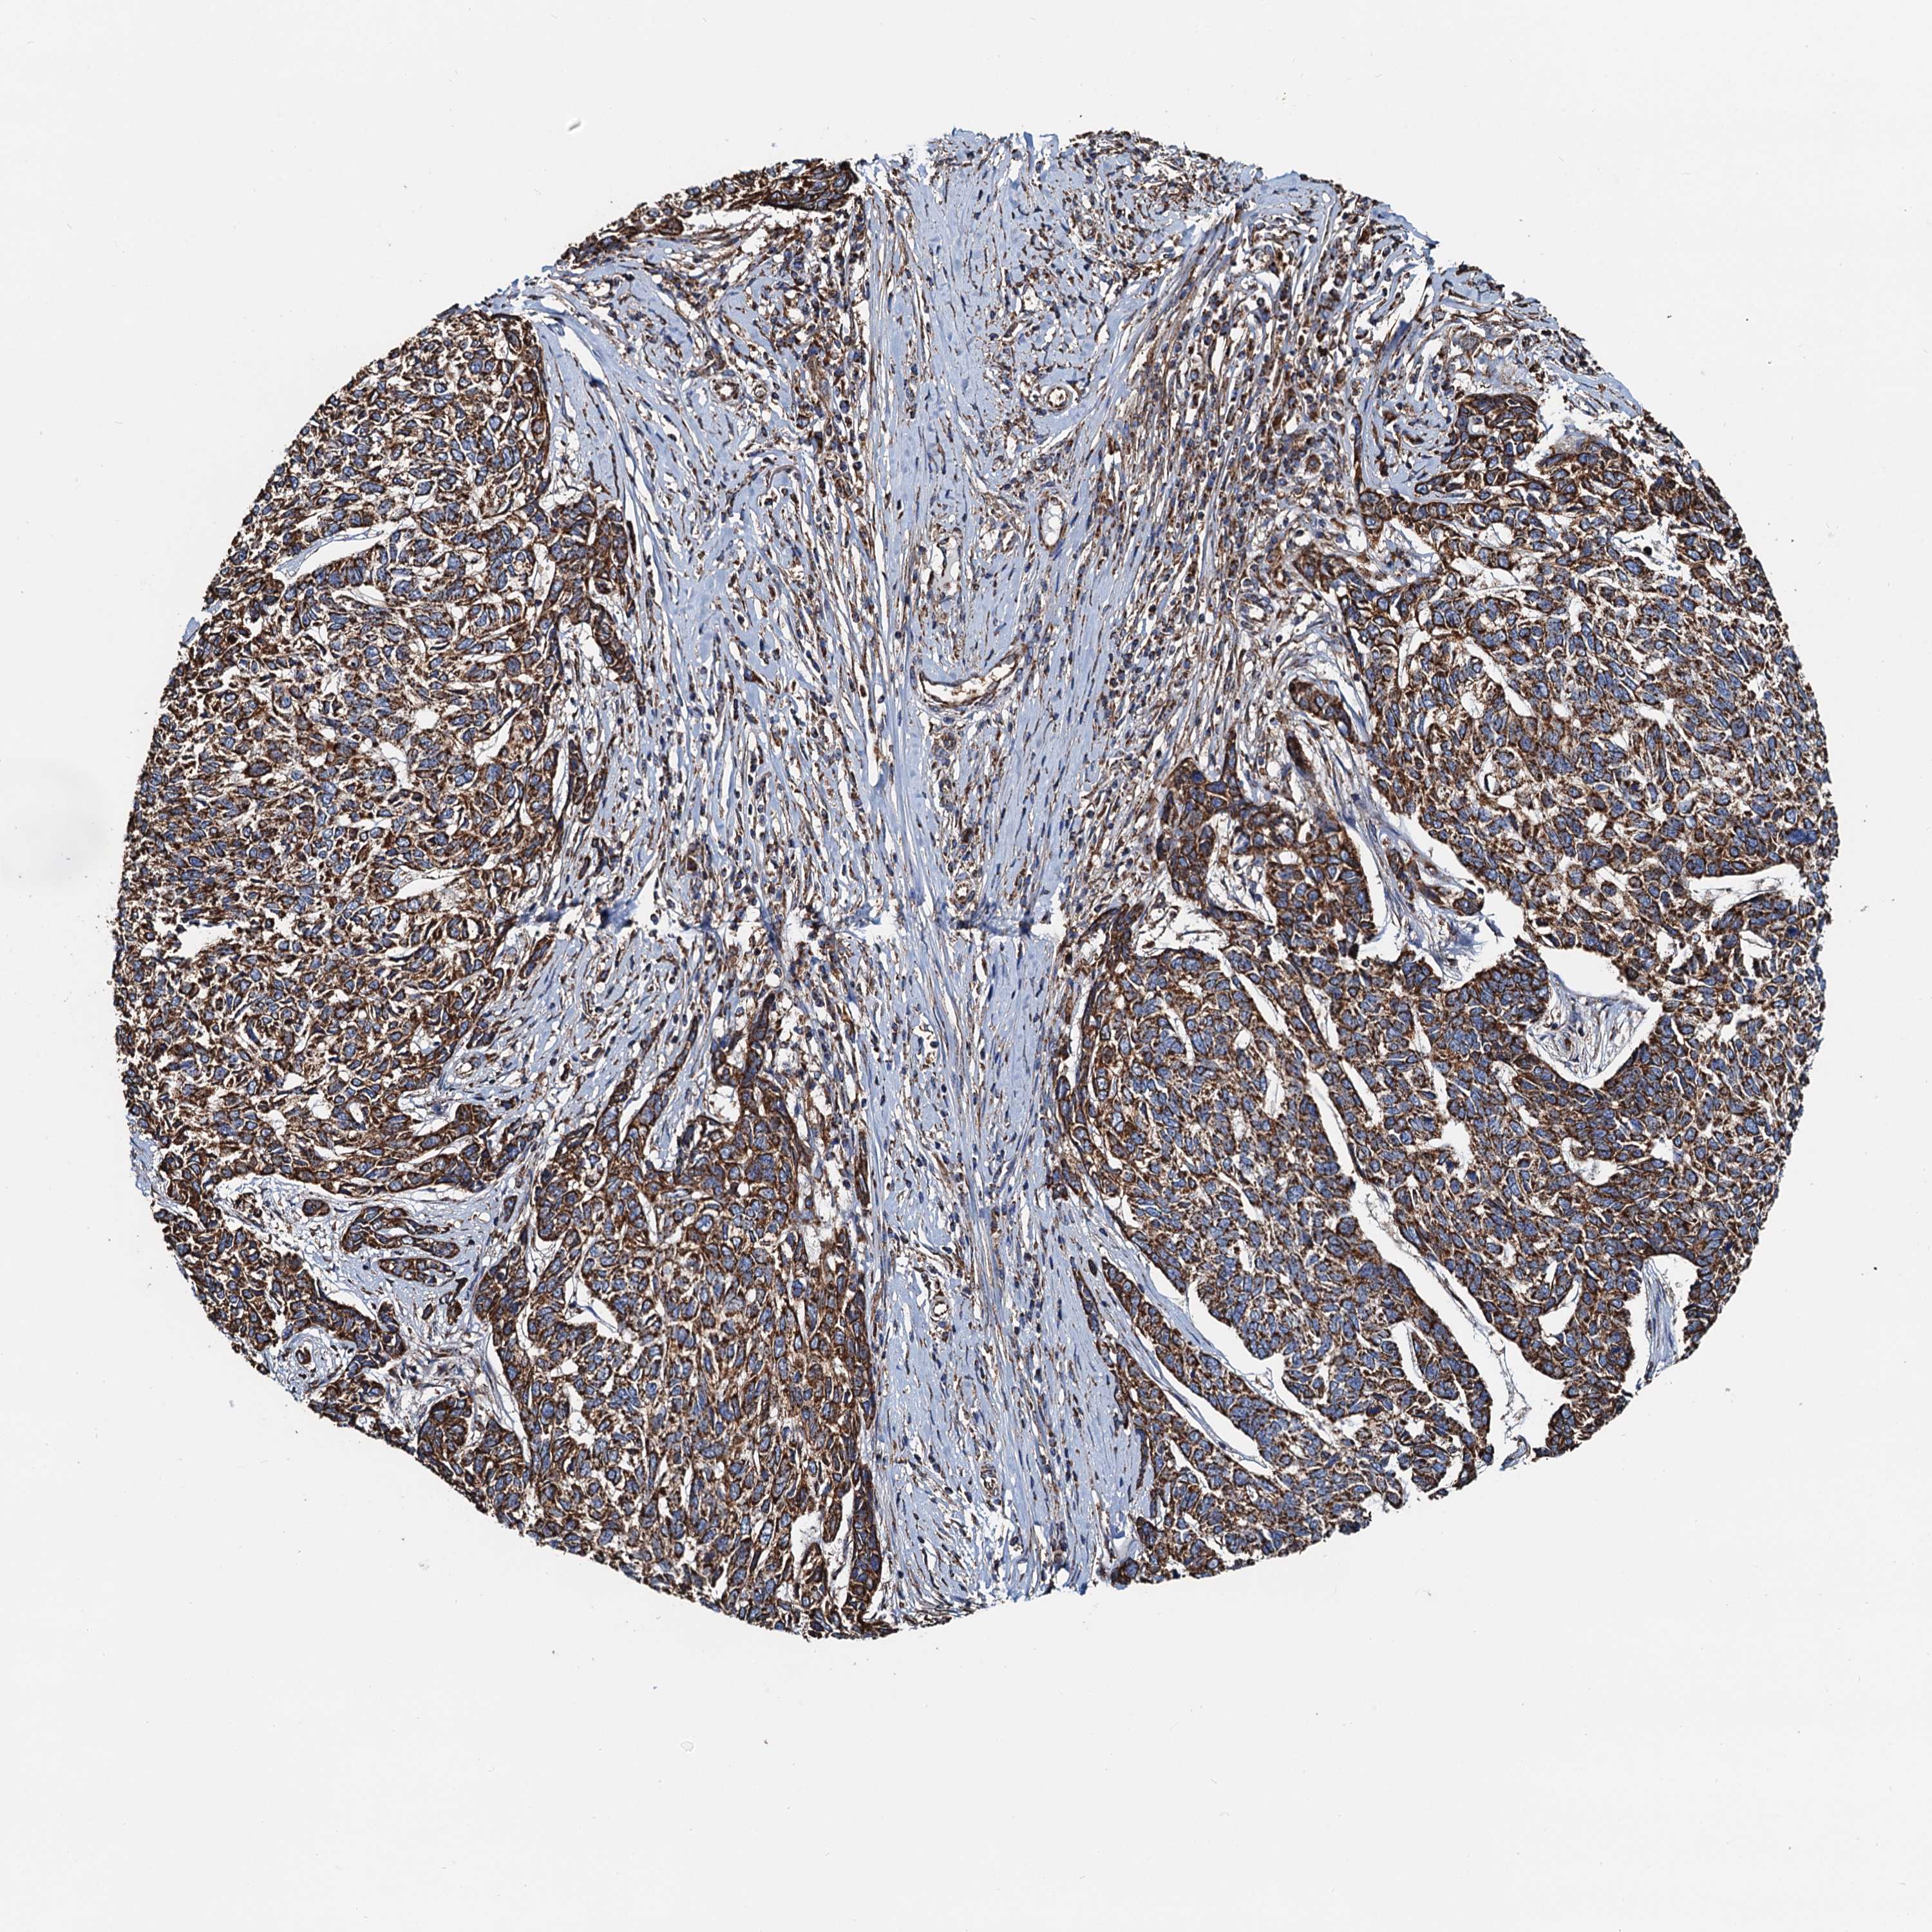

Basal cell and squamous cell cancer

SKIN CANCER - Protein expressioni

A mouse-over function shows sample information and annotation data. Click on an image to view it in a full screen mode. Samples can be filtered based on level of antibody staining by selecting one or several of the following categories: high, medium, low and not detected. The assay and annotation is described here.

Antibody stainingi

Antibody staining in the annotated cell types in the current human tissue is reported as not detected, low, medium, or high, based on conventional immunohistochemistry profiling in selected tissues. This score is based on the combination of the staining intensity and fraction of stained cells.

Each image is clickable and will lead to virtual microscopy that enables deeper exploration of all samples and also displays staining intensity scores, fraction scores and subcellular localization as well as patient and tissue information for each sample.

Antibody HPA039371

Antibody HPA040174

Staining

High

Medium

Low

Not detected

Intensity

Strong

Moderate

Weak

Negative

Quantity

>75%

75%-25%

<25%

None

Location

Nuclear

Cytoplasmic/membranous

Cytoplasmic/membranous,nuclear

Basal cell carcinoma

Squamous cell carcinoma, NOS

Squamous cell carcinoma, metastatic, NOS